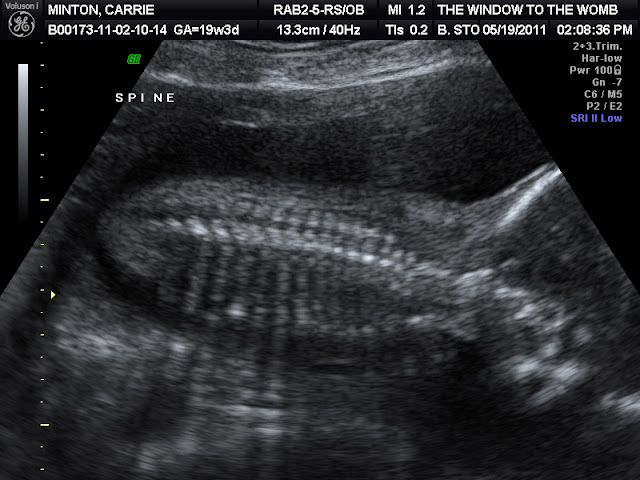

We went for my 20 week ultrasound on May 19th. Max was in a great mood until he tripped in the waiting room and hit his cheek on the coffee table. The sonographer called us back shortly afterward, and Max was a wreck the whole appointment. Travis' time was spent trying to keep him happy, while our littlest one gave the sonographer a run for her money. She tried several times through the appointment to see if it was a boy or girl, and this baby was a lot more modest than Max was. At the end of the appointment she was finally able to see what she was looking for. I thought I saw it before she said anything...It's a boy! Max is going to have a little brother! We are thrilled for him and have hopes that they'll be great friends! Here are some photos from our big day!

Spine